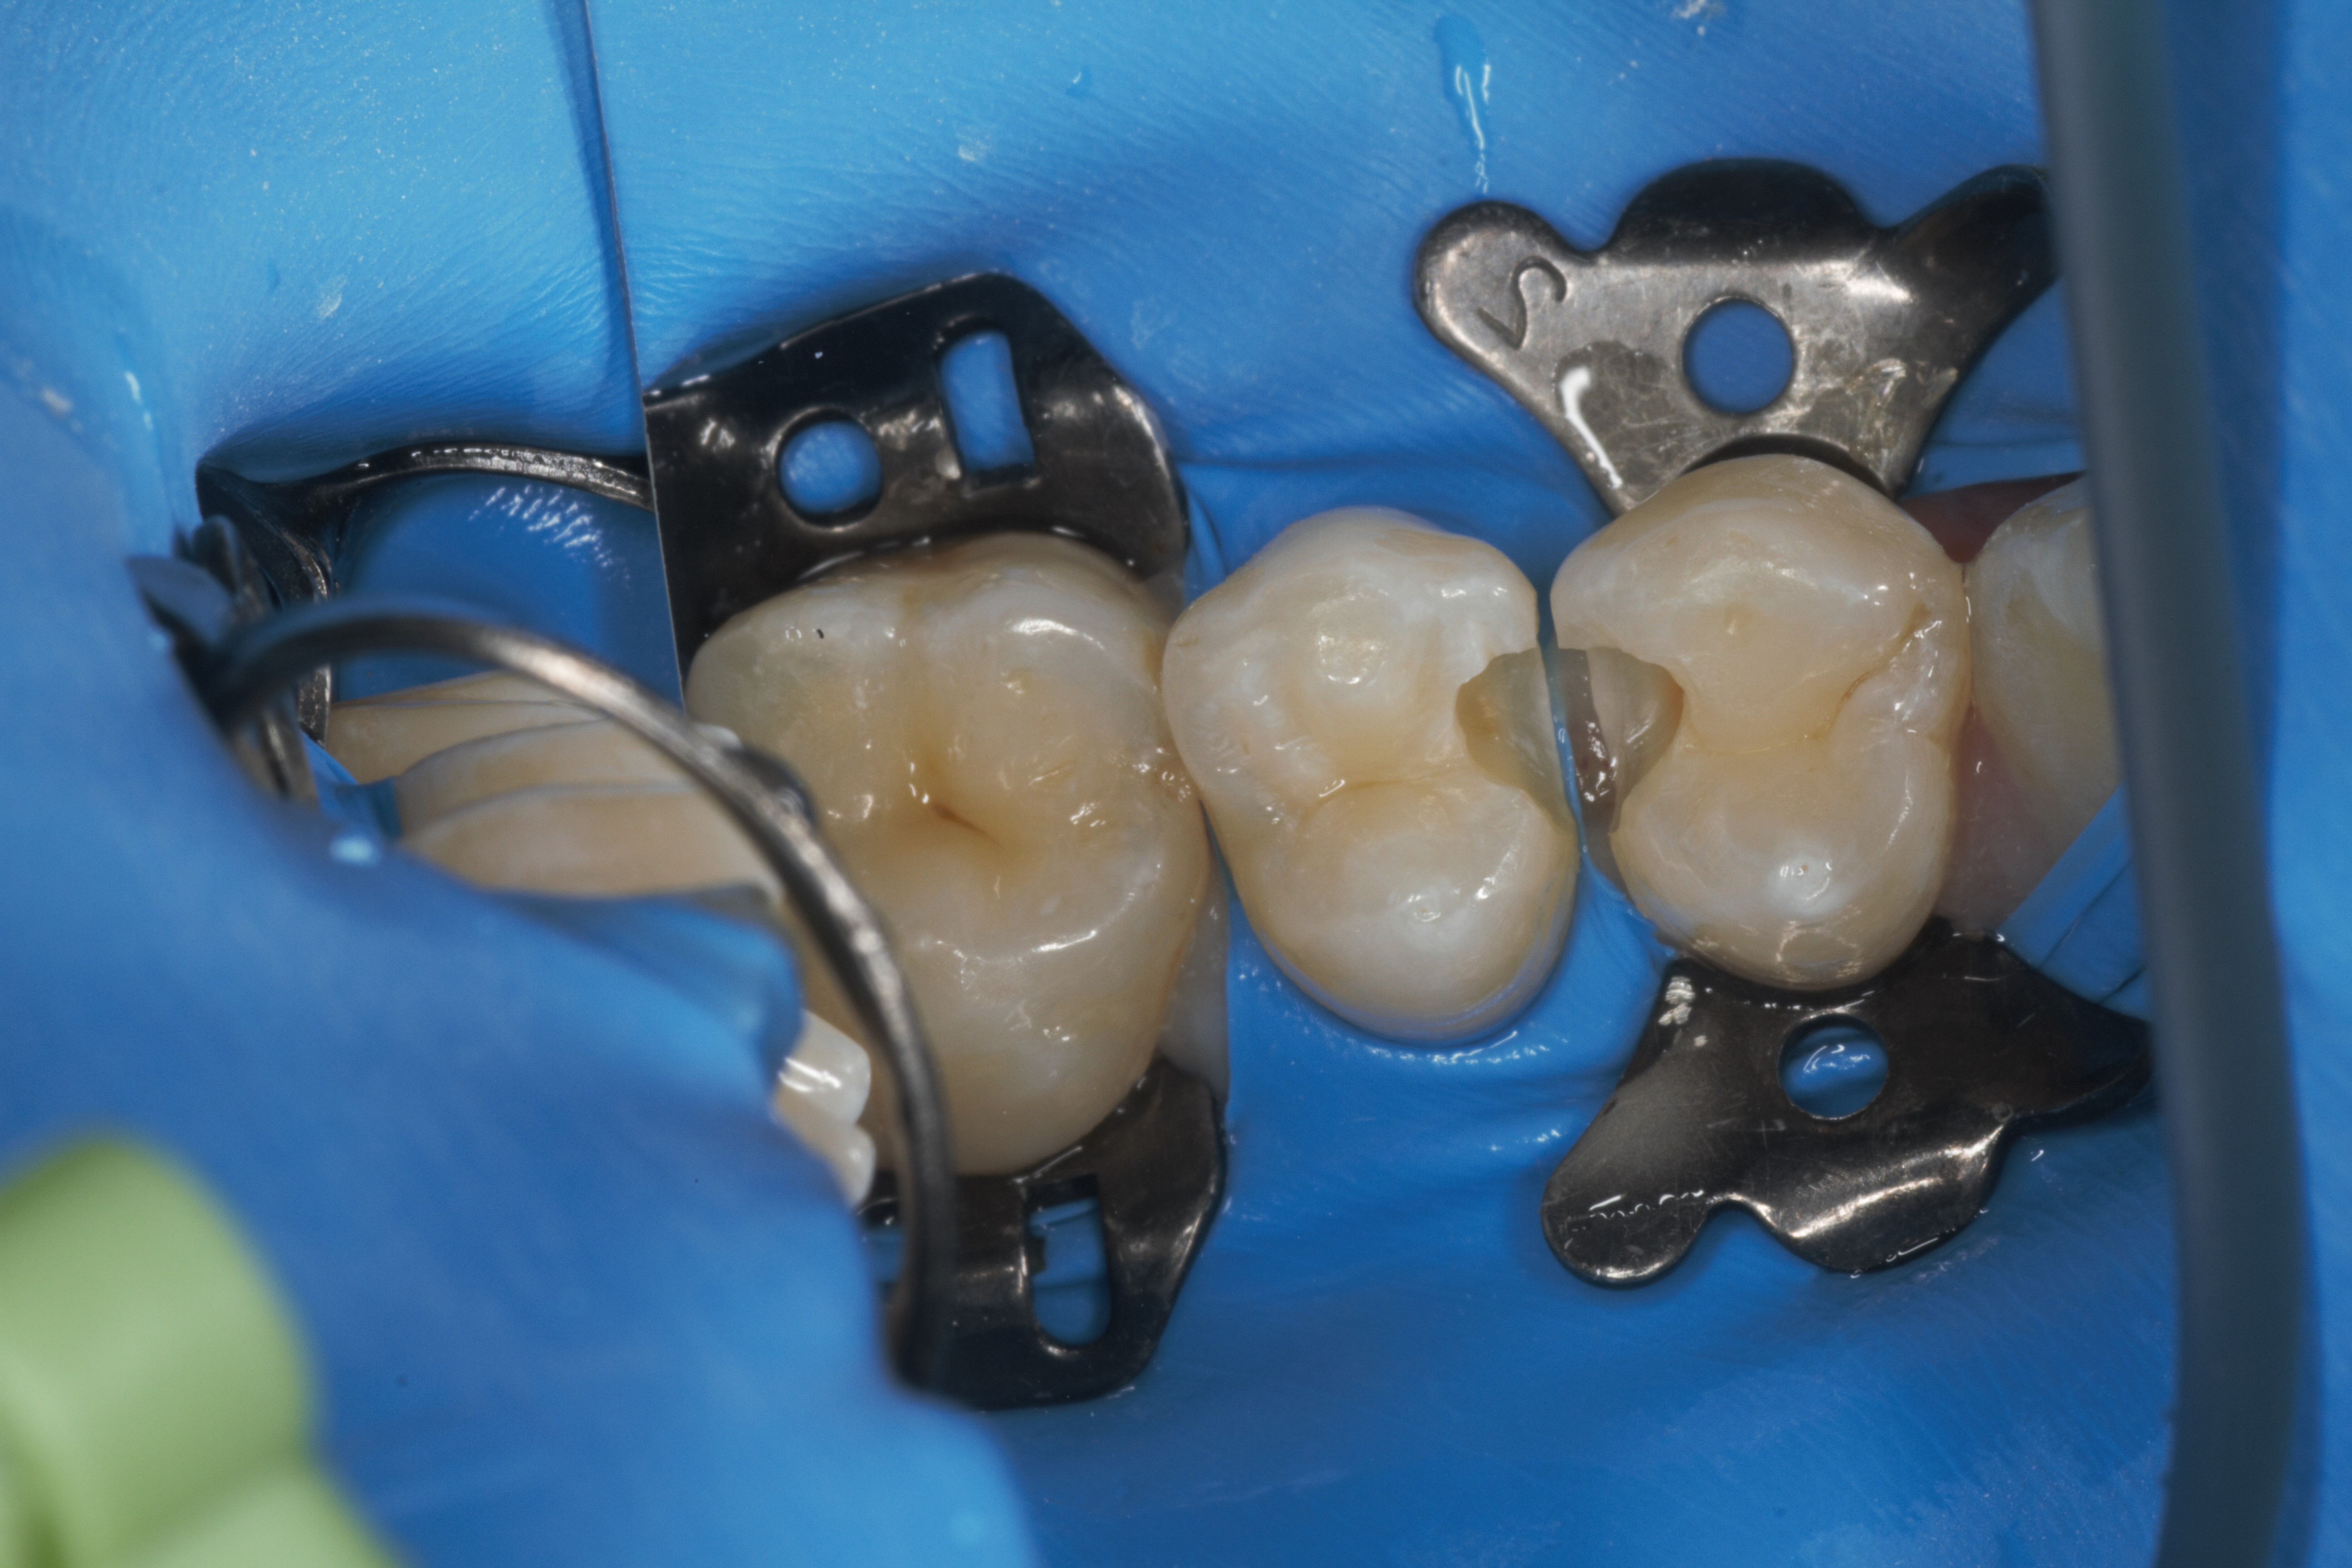

- Эстетическая реставрации жевательной и фронтальной группы зубов современными пломбировочными материалами, диагностика кариеса на ранних этапах развития, предупреждение образования вторичного кариеса в области запломбированных зубов